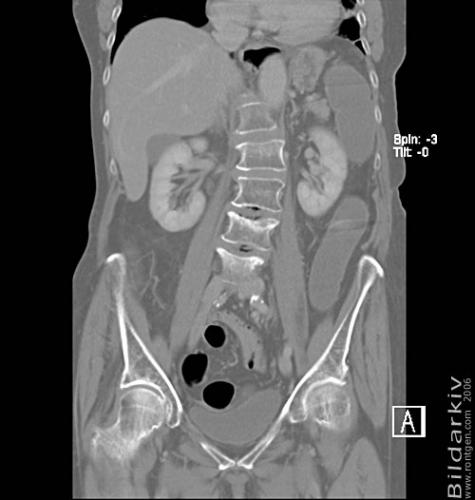

CT colon 29

Datortomografi av tjocktarmen (colon) med infunderad luft i tarmen samt med kontrast i blodbanan. Koronar bildserie.

CT multislice 16